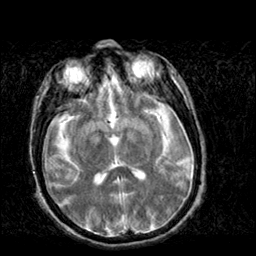

Creutzfeld-Jakob disease: T2-weighted MR -- Slice #12

[Home][Help][Clinical] Slice 12